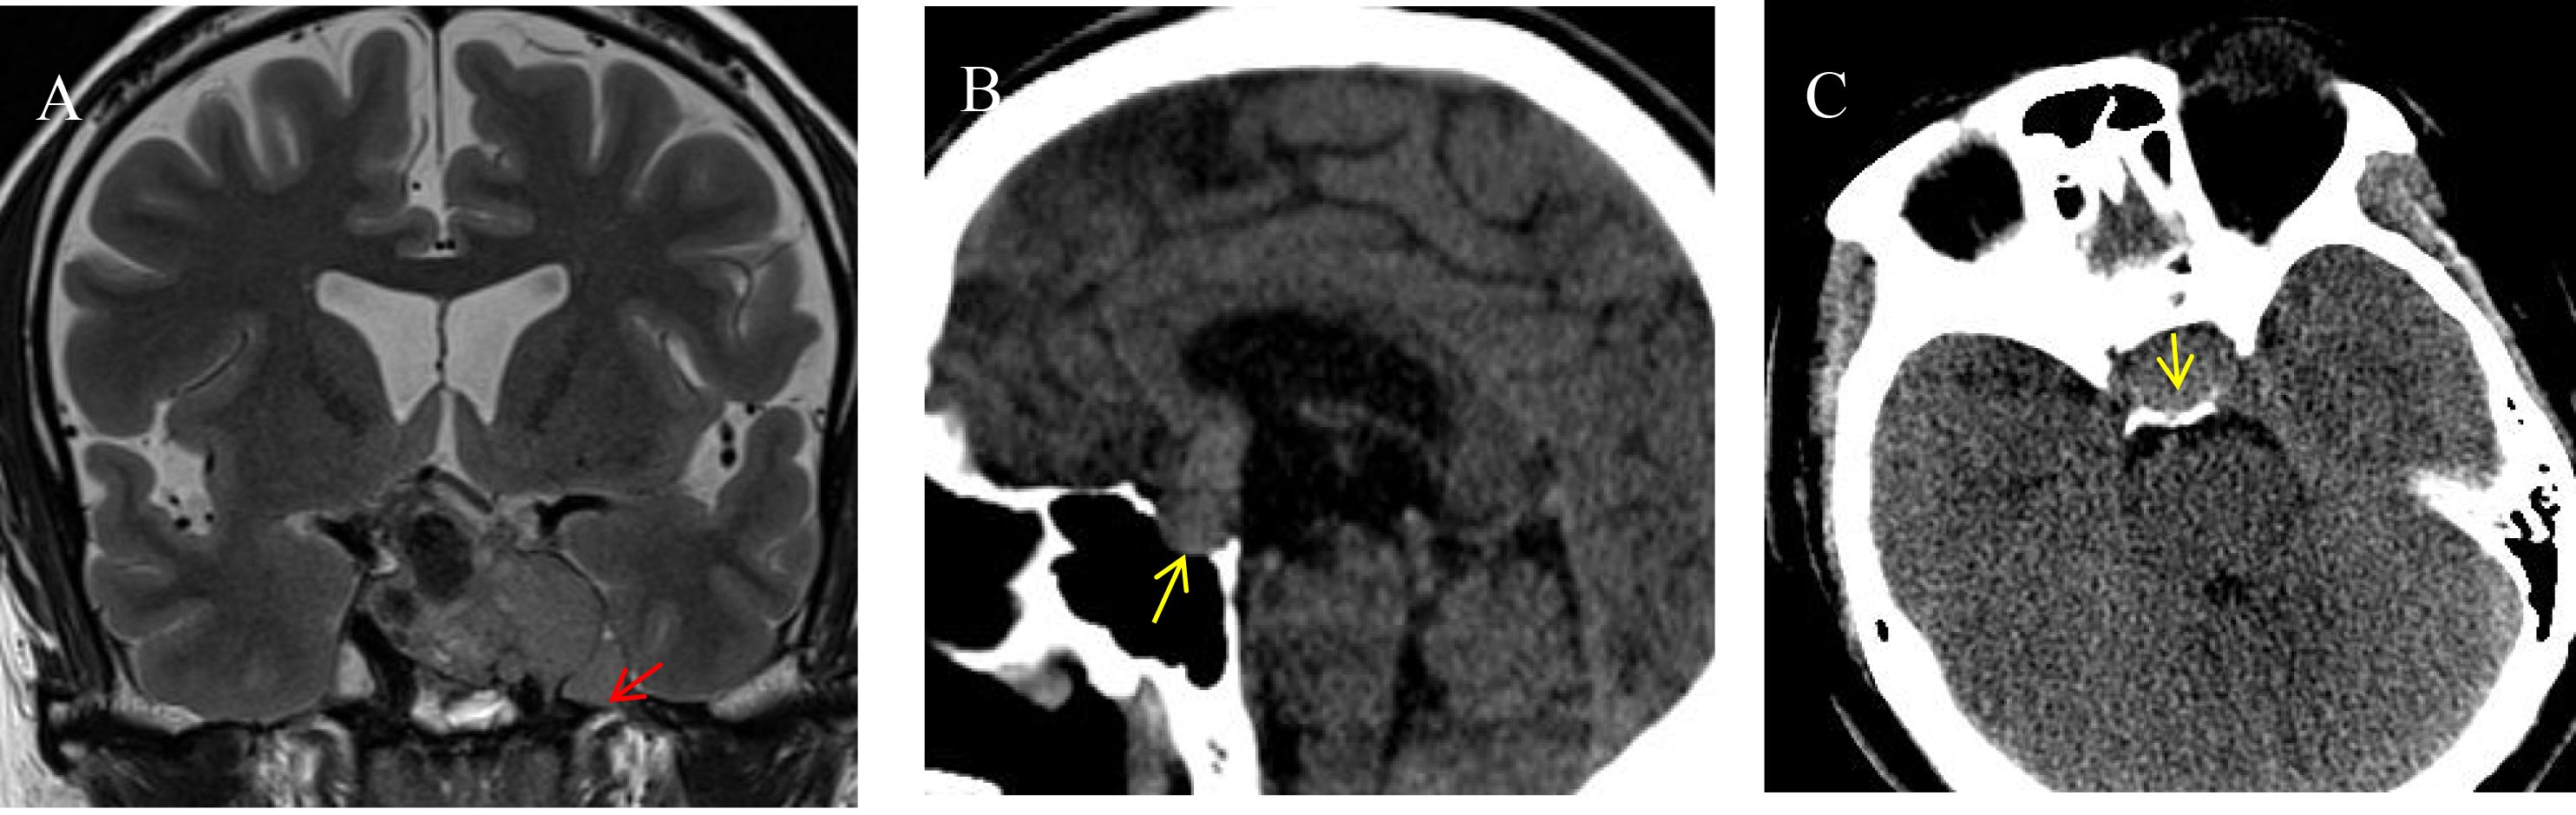

Objective: This study aims to develop a predictive model for cavernous sinus dural invasion in pituitary adenomas by retrospectively analyzing clinical and imaging data. It explores the associations between clinical and radiomics features and cavernous sinus dural invasion. Methods: Clinical data and coronal T2-weighted MRI images were collected from patients diagnosed with pituitary adenomas at our institution between December 2012 and December 2022. Tumor regions of interest (ROIs) were segmented using 3D Slicer, and radiomics features were extracted. Statistically significant radiomics features were identified using Lasso regression and univariate analysis. Clinical features were screened using univariate and multivariate logistic regression analyses. These selected features were incorporated into ten machine learning algorithms to construct three predictive models: a clinical feature model, a radiomics feature model, and a combined clinical and radiomics feature model. Model performance was evaluated to determine the best-performing model, which was further interpreted. Results: A total of 252 patients with histopathologically confirmed pituitary adenomas were included. The analysis identified Knosp grade, tumor left-right diameter, pedunculated satellite tumor, and clival invasion as significant clinical predictors, along with radiomics features including original.4, original.10, log-sigma-5-0-mm-3D.29, log-sigma-5-0-mm-3D.91, wavelet-LLH.37, wavelet-LHL.37, and wavelet-HLL.8. The combined clinical and radiomics model outperformed models based solely on clinical or radiomics features. Among the ten machine learning algorithms, the LightGBM model demonstrated the best predictive performance, achieving an area under the curve (AUC) of 0.86 and an accuracy (ACC) of 0.76. Conclusions: A machine learning model integrating clinical and radiomics features can effectively predict cavernous sinus dural invasion in pituitary adenomas preoperatively, providing a reliable basis for diagnosing tumor invasiveness and developing surgical plans. The LightGBM algorithm exhibited the highest predictive efficacy. Furthermore, the pedunculated satellite tumor feature emerged as a novel imaging marker for cavernous sinus dural invasion, offering new insights into the study of invasive pituitary adenomas.